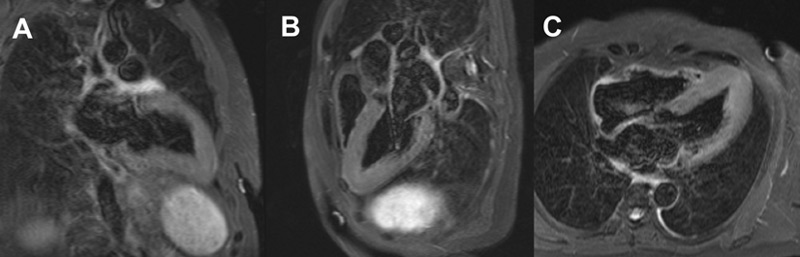

Figure 1 : Séquence T2 STIR, coupes 2 cavités (A) 3 cavités (B) et 4 cavités (C)

Présence de cryptes myocardiques dans la région septo-apicale (flèche). Ces cryptes peuvent aider à définir les porteurs de mutations de CMH ne présentant pas d’hypertrophie du VG.

Astuces pratiques : retenez que les cryptes myocardiques peuvent facilement être manquées sur les vues petit axe (ce qui est aussi le cas pour ce cas clinique) en raison d’un effet de volume partiel qui fait disparaitre la crypte.